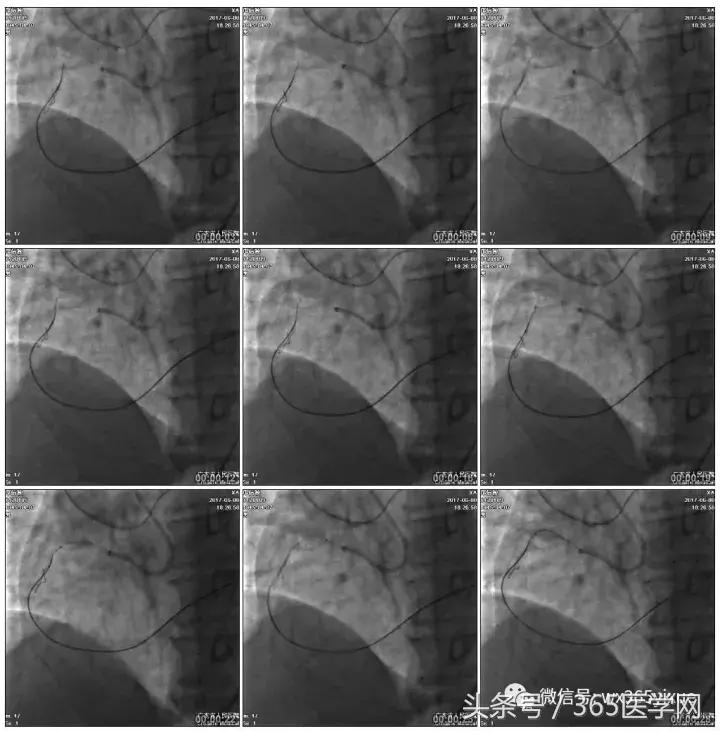

正向浅尝,改为逆向,LCX-PL

RRA:6F AL0.75 GC –RCA;

RFA:7F XB 3.5 GC—LCA 150cmcorsair

正向130cmFinecross微导管支持下尝试送PILOT150、Gaia 2导丝无法通过RCA闭塞段

SION导丝通过侧枝

逆向导丝:更换Gaia2

正向导丝:Gaia2,PILT150

正向导丝knuckle

2.5*15mm球囊扩张,逆向导丝尝试,但未能进入正向GC

1.正向2.5*15mm球囊扩张,Reverse CART

2.Guidezilla延长导管辅助下,逆向导丝进入正向GC